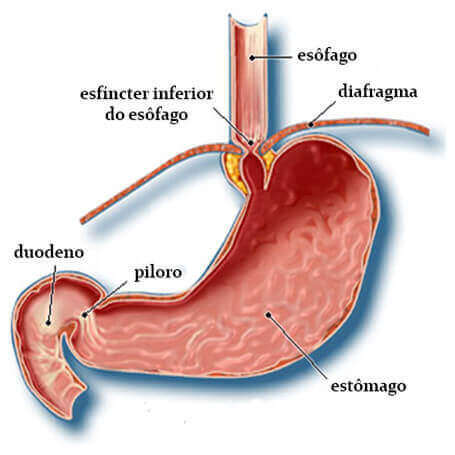

Na transição esofagogástrica, ou seja, no final do esôfago, existe uma estrutura muscular semelhante ao ânus chamada de esfíncter esofágico inferior (EEI). Quando deglutimos o alimento, o EEI se abre dando passagem ao bolo alimentar. Na ausência da deglutição o EEI permanece fechado e tem um tônus (pressão) que impede o refluxo dos alimentos do estômago para o esôfago. A transição esofagogástrica deve se situar no abdome para que a crura diafragmática participe externamente deste mecanismo funcionando como uma válvula.

O tórax e o mediastino são separados do abdome por uma estrutura fibromuscular chamada de diafragma. O hiato diafragmático é o orifício ou abertura do diafragma por onde passa o esôfago. A transição esofagogástrica normalmente se situa imediatamente abaixo do diafragma e, quando esta está posicionada acima dele, estamos diante da hérnia de hiato: